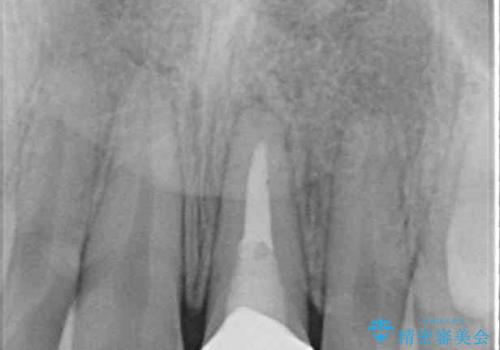

長時間のマウスピース装着と、患者様自身でのゴムかけに協力いただき、口元の突出感をしっかりと改善することができました。

前歯のオールセラミッククラウンもまるで本物の歯のように仕上がり、患者様には大変満足していただきました。